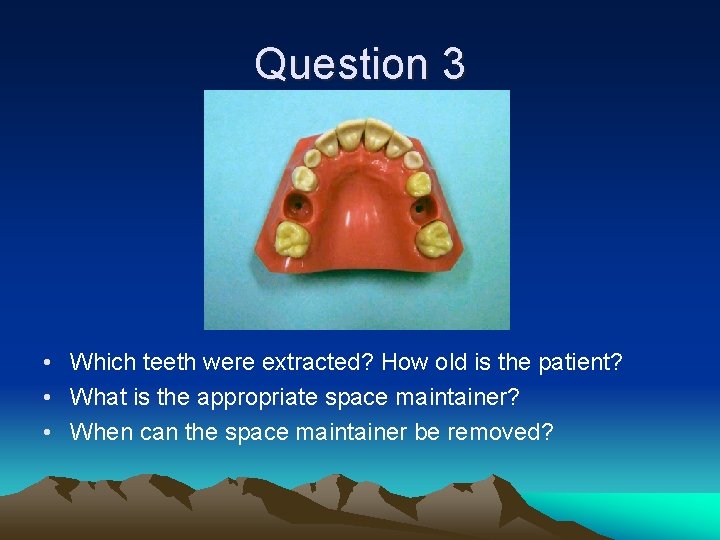

Question 3 • Which teeth were extracted? How old is the patient? • What is the appropriate space maintainer? • When can the space maintainer be removed?

Question 3 • Teeth #A and #J extracted. Patient 8 -9 y. o.

Question 3 • Nance #3 -#14 • Can be removed when #4 and #13 erupt-around age 12